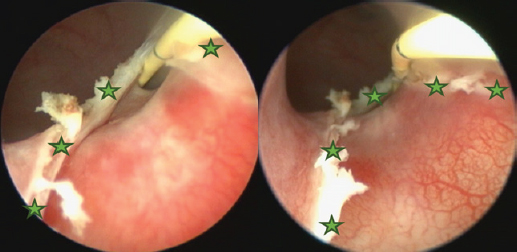

The surgery aimed to cut the outer ureteral membrane and redirect left kidney-produced urine from the urethra to the bladder. Before cutting, a hydrophilic 3 Fr catheter was introduced through a pathologic left ureter opening. It worked as a guide to fully visualize the intramural ureteral tunnel. After that, a Karl Storz monopolar coagulating ball electrode (3 Fr × 53 cm) was introduced through the working channel of the cystoscope sheath. The electrode cut the medial aspect of the ureteral wall up to the bladder trigone, where the contralateral normal ureter opens. The cut membrane did not bleed during the surgery (Figs. 68).

Fig. 7. Cystoscopy pictures where green stars indicate edges of the cut ureteral membrane. A yellow 3 Fr guide catheter is seen on the right side of both pictures.

Fig. 8. Cystoscopy picture taken after cutting the ureteral membrane (see the green stars). A 3 Fr pigtail type catheter is outlined in red; it is curled inside the urinary bladder.